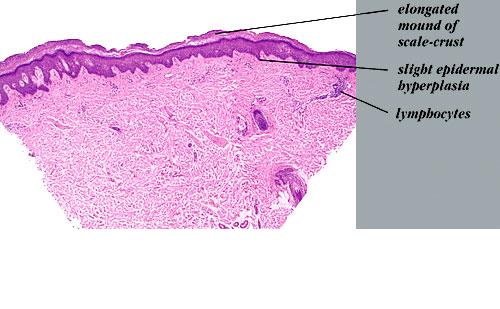

Graft versus Host Disease =داء رفض الطعم للمضيف Graft Versus Host Disease GVHD occurs in situations in which donor immunocompetent T cells transferred into allogenic hosts are incapable of rejecting them. The sources of the T cells include primarily peripheral blood stem cell and bone marrow transplants and, infrequently, unirradiated blood products , solid organ […]